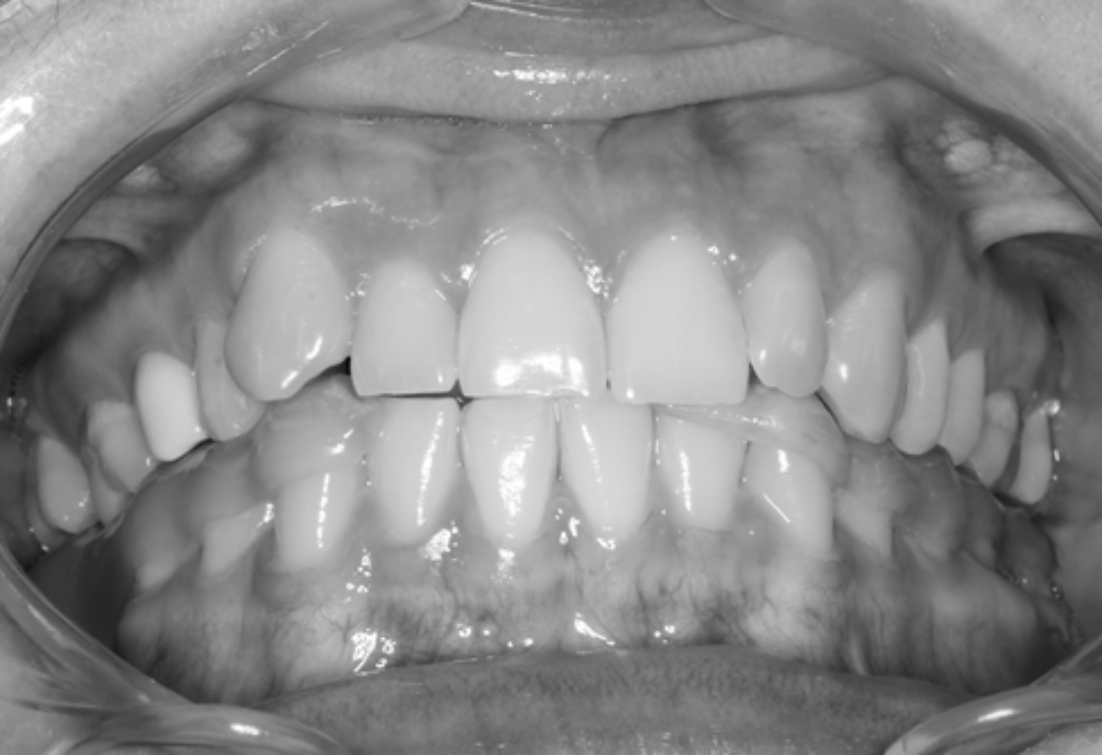

In the oral cavity: the mucosa is without visible pathological changes, the anterior teeth of the upper jaw overlap the same teeth of the lower jaw by 1/2 of their height, vestibular displacement 1.3, 2.2, crowded arrangement of the anterior teeth of both jaws.

The closure of the dental arches in the position of central occlusion is sharply hampered with a distal and rightward shift at the end of mouth closure.

Completion of orthodontic treatment was accompanied by the removal of the bracket system with the installation of retainers on the oral surface of the anterior teeth of the upper and lower jaws, as well as prosthetics with an artificial crown on an implant in the area of the missing 4.6 (Fig. 9).

Fig. 9. Closing of the dental arches after completion of treatment